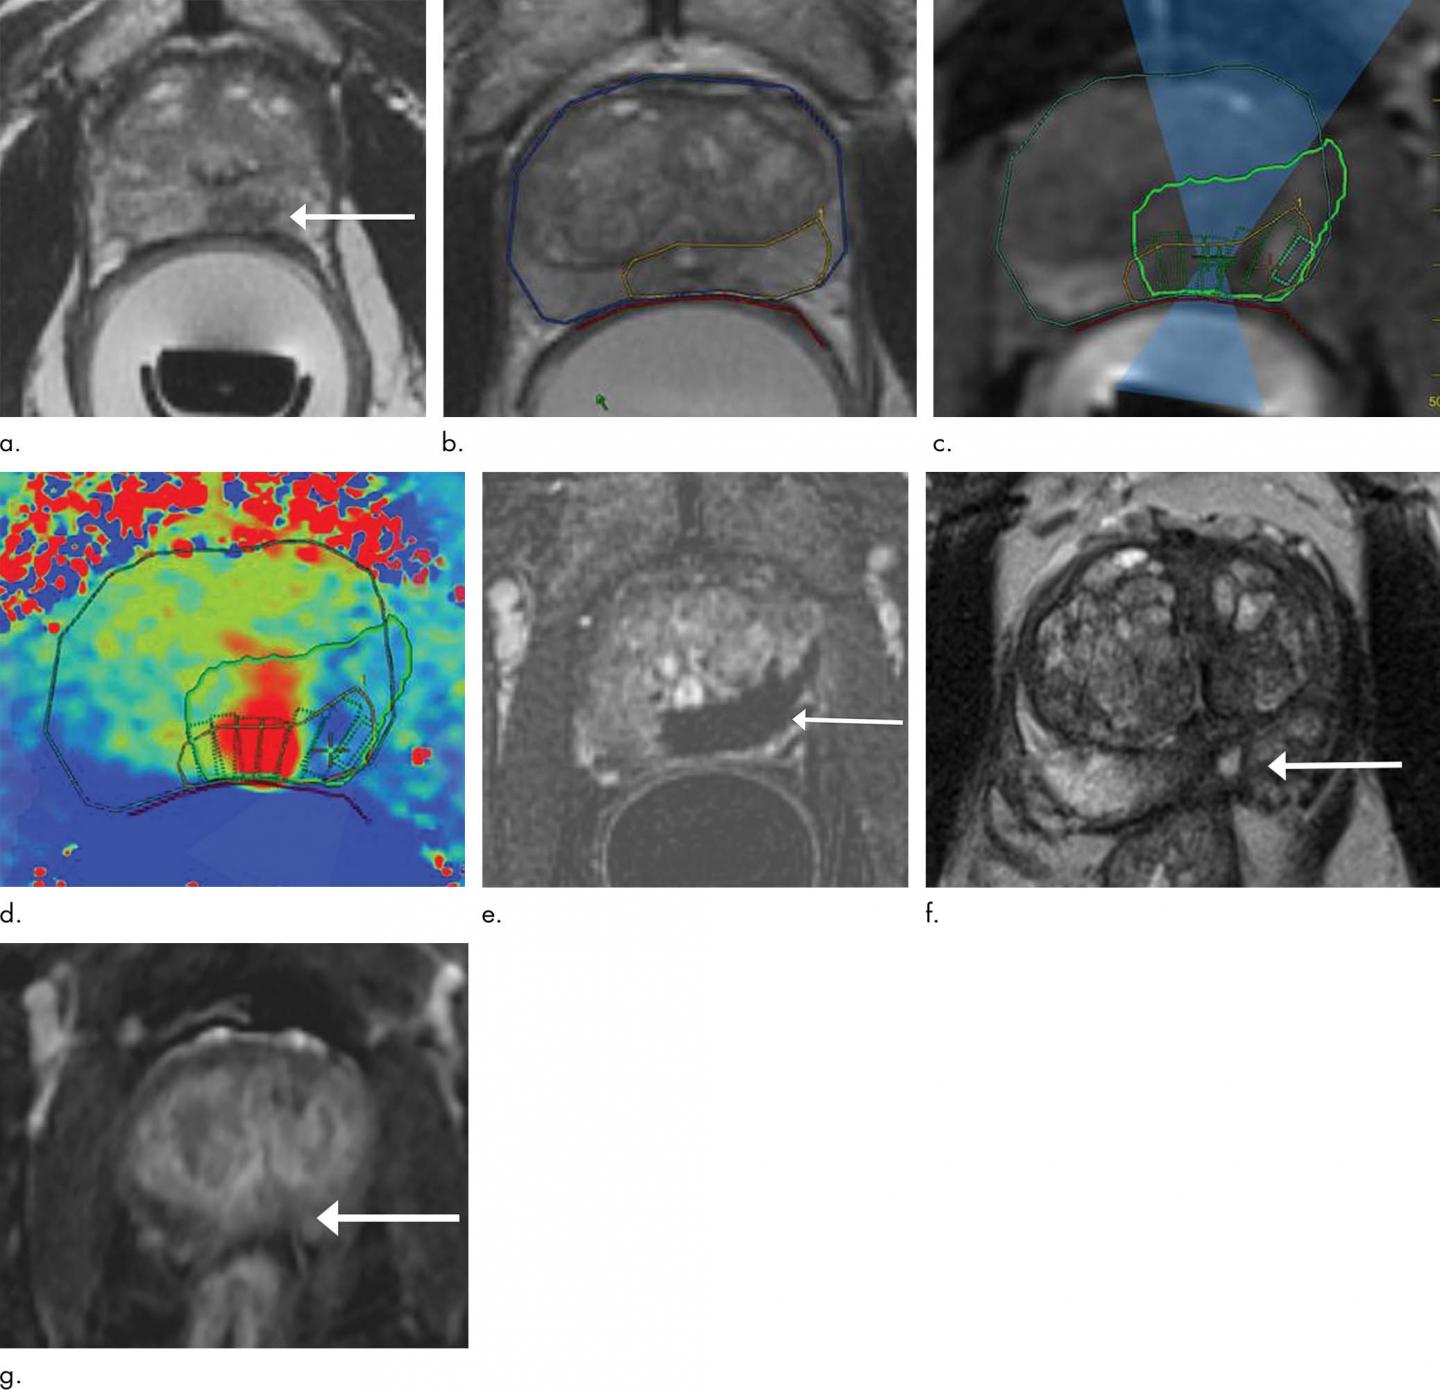

For the new study, researchers studied a device that delivers MRI-guided focused ultrasound (MRgFUS). While the patient is under general anesthesia, a probe is placed in the rectum that focuses high-frequency ultrasonic waves to the site of the cancer. The procedure takes approximately four hours to perform.

"By combining the high-intensity focused ultrasound device with MRI, we can target our treatment to the exact location, because we're able to pinpoint precisely where the tumor is," said the study's principal investigator and lead author Sangeet Ghai, M.D., at Toronto's Joint Department of Medical Imaging, part of the University Health Network (UHN) Sinai Health and Women's College Hospital.

Although MRgFUS requires additional expertise, resources and cost, it has several key advantages over other approaches. Use of MRI allows for thermal feedback during treatment, an important consideration since killing the cancerous tissue requires a temperature of more than 60 degrees Celsius.

"MRI almost instantaneously gives feedback as to the temperature that we've been able to achieve at the site," Dr. Ghai said. "If the temperature was not what I wanted to get, I can reheat that area so that chances for successful treatment increase."

An additional benefit of MRI is that it can show if there is any remaining vascularity in the treatment area, a sign that not all the cancer has been eradicated.